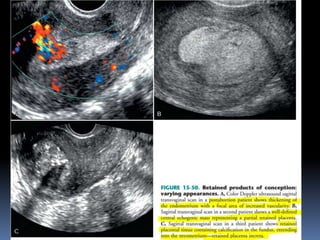

This document contains an image gallery from Dr. Mohit Goel showing various uterine anomalies and ovarian cysts. It includes images of an arcuate and unicornuate uterus, endometritis, a twisted ovarian pedicle, dermoid cysts of varying sizes and echogenicity containing hair, fat, and calcifications, and a combination dermoid cyst showing both mesh and plug structures. The gallery provides ultrasound images of different gynecological conditions for medical education and reference.